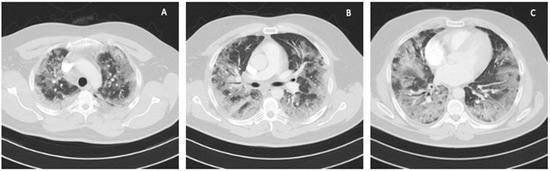

A 41-year-old obese man with BMI = 31.5 kg/m2 (class I obesity), without comorbidities, was admitted to the ICU due to symptoms of respiratory failure worsening as a result of SARS-CoV-2 infection. On admission to the ICU, a chest CT angiography scan was performed, showing signs of pulmonary embolism and ground-glass opacity inflammatory lesions, affecting up to 80% of the lung parenchyma (Figure 1).

Figure 1. Chest CT scan on admission to the ICU: (A) upper lung segments; (B) middle lung segments; (C) basal lung segments (Case 1).